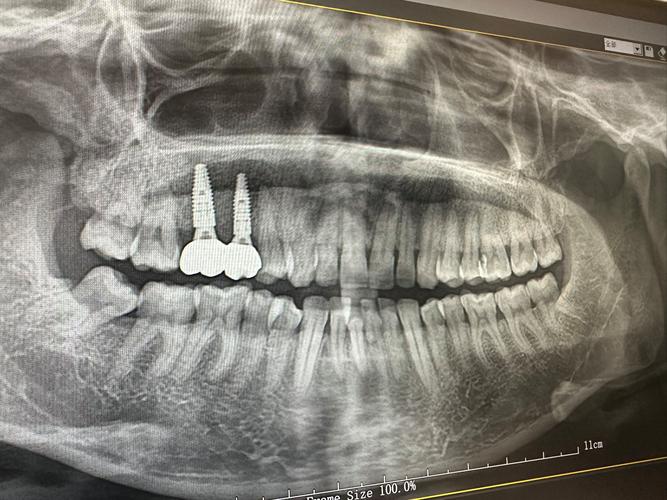

正畸治疗依赖牙槽骨的改建能力:牙齿移动时,牙槽骨一侧吸收、一侧增生,若骨量不足,吸收速度可能超过增生速度,导致牙根暴露、牙齿松动,甚至骨开裂,对于中重度牙槽骨薄患者,正畸前需通过CBCT等影像学评估骨量,判断是否需要植骨,轻度骨薄可通过轻力移动、延长矫正周期等策略调整,但中重度骨薄(如骨厚度<1mm)则需植骨增加骨量,为牙齿移动提供足够支持。

植骨时机需个体化设计:常见方案有三种,一是正畸前植骨(引导骨再生GBR),先植骨等待3-6个月骨结合完成后再正畸,适用于骨量严重不足者;二是正畸中植骨,在牙齿移动过程中同步进行局部植骨,缩短治疗周期;三是正畸后植骨,针对矫正后美学区骨量不足,改善牙龈形态,无论哪种方案,术后均需保持口腔卫生,避免咀嚼硬物,定期复查骨愈合情况。